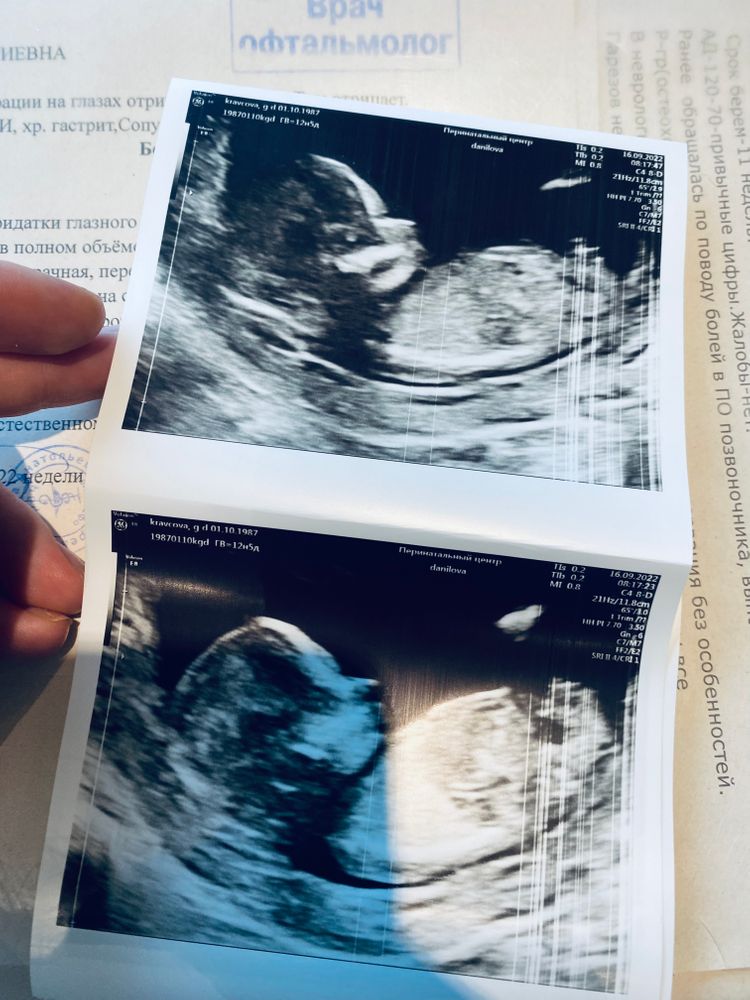

14 неделя уже 😍 и 1 скрининг

Всё о нашей беременностиСегодня мы прошли 1 скрининг наконец-то 🥳

По акушерскому сроку 12.5 сегодня, но на всех УЗИ мы идём +5/6 дней, так что нам поставили 13,3 недели ❤️

У мелкого все на месте , риски по ТВП и носовой кости отсутствуют 😮💨подтвердили мальчика 👶☺️

И наше фото (нос в папу 100%😁)